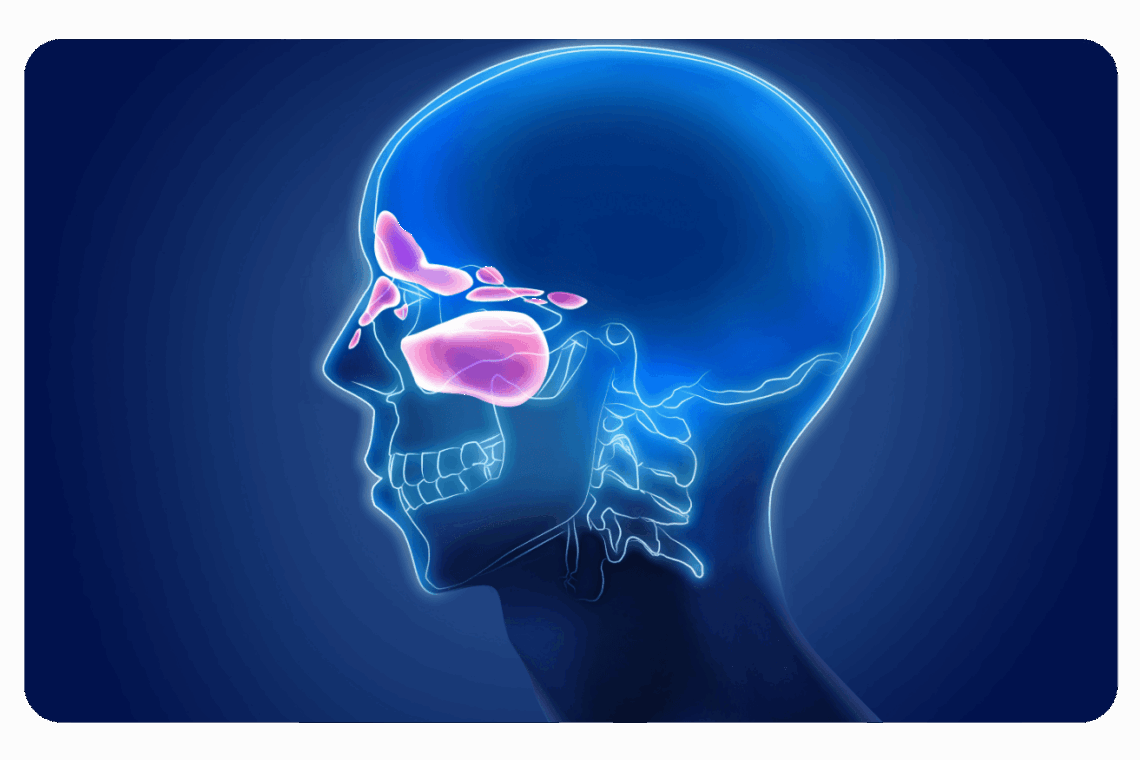

Sinusite : Traitement efficace, symptômes et solutions naturelles

La sinusite représente une inflammation des muqueuses tapissant les sinus paranasaux, ces cavités osseuses reliées aux fosses nasales. Cette affection touche environ 15% de la population européenne chaque année et constitue l'une des pathologies ORL les plus fréquentes en consultation. Au-delà de la gêne occasionnée, la sinusite peut considérablement altérer la qualité de vie quotidienne, avec des symptômes parfois invalidants comme des maux de tête persistants, une congestion nasale ou une fatigue chronique.